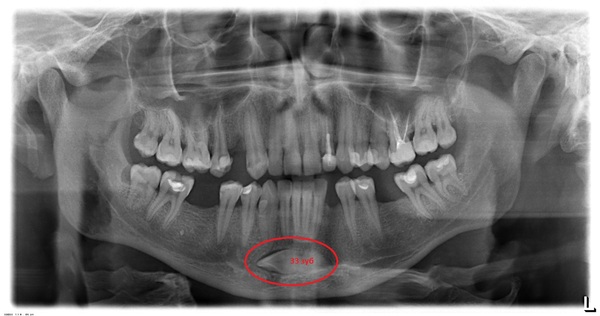

Четвертый снимок

Здесь автор "Запасные зубки" пишет про херню в подбородке. Эта херня - 33 зуб, ретинированный и дистопированный клык нижней челюсти. И знаете что я вам скажу по поводу этого этого? Я не был бы рад херне в подбородке.

По итогу хочу сказать, что ни на одном снимке нет гипердентии, как утверждает Rentgenologia. Снимки - интересные, вот только представлены, к сожалению, не грамотно. А вообще, на мой взгляд, когда человек освещает какую-то тему, то он должен отчасти нести ответственность, и должен быть компетентным, что не видно в посте "Запасные зубки".